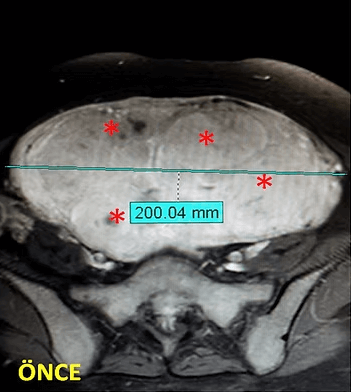

41 yaşında, kabızlık, gaz ve sık idrara çıkma şikayetleri var. Emar’da karını dolduran dev miyom (*) mevcut. Miyomektomi önerilmiş, ancak operasyonda rahimin alınabileceği söylenmiş. Embolizasyondan sonra dev miyomun ve bir başka küçük miyomun öldüğü ve küçüldüğü izleniyor. 7 ay sonra hasta şikayeti kalmamıştır.